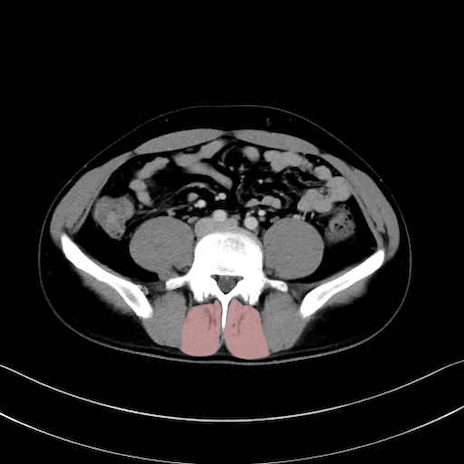

多裂筋 (Multifidus)